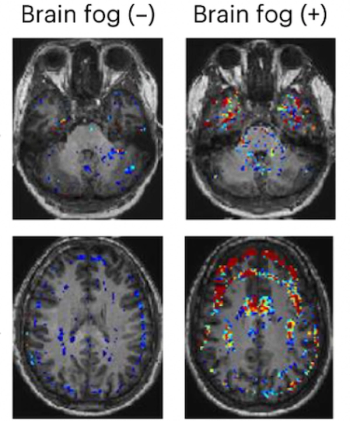

For people with COVID-19 related brain fog, emerging dynamic contrast-enhanced MRI (DCE-MRI) research findings revealed blood-brain barrier disruption in multiple brain regions, including temporal lobes and the frontal cortex, up to a year after active infection.